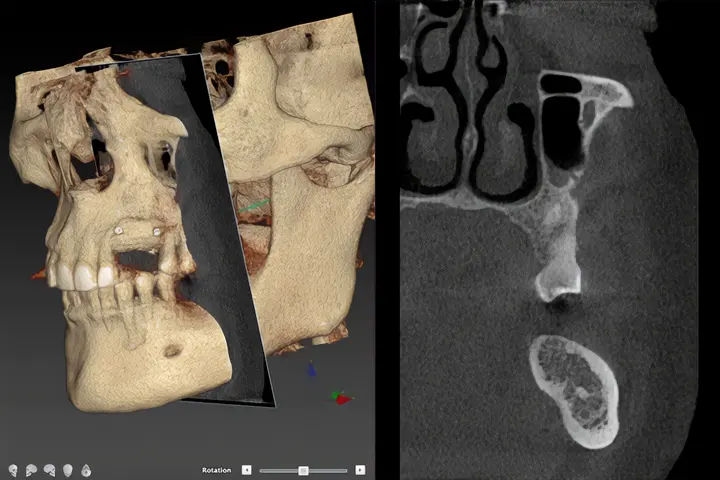

Digital Implant Workflow and Virtual Planning

Industry partnerships are aimed at integrating digital innovation into surgical protocols:

- Virtual planning platforms

- AI software development

- Digital scanning for monitoring implant health

- Guided surgery systems

- CAD-CAM design and 3D-printed grafts and fixtures.

Focus: precision, minimally invasive execution, and predictable outcomes.